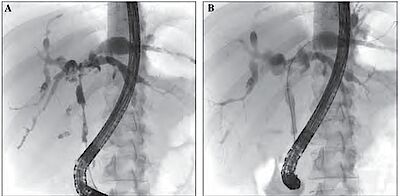

Die Diagnose der PSC beruht nach Ausschluss anderer Ursachen, insbesondere der sekundär sklerosierenden Cholangitiden, auf dem Nachweis der erhöhten Cholestaseparameter und der Darstellung der typischen Gallenwegsveränderungen in der ERCP oder MRCP (siehe Kasten und Abbildungen). Die Leberbiopsie zeigt typische konzentrische Fibrosierungen „zwiebelschalenartig“ um die Gallenwege, jedoch kann die Biopsie die Erkrankung nicht sicher ausschließen, da auch bei fortgeschrittener Erkrankung das Lebergewebe an einigen Stellen noch normal aussehen kann.

Eine wirksame medikamentöse Therapie steht bislang nicht zur Verfügung (siehe auch „Aus Wissenschaft und Forschung“, S. 24 in diesem Heft). Ursodesoxycholsäure bessert zwar die Cholestaseparameter und den Ikterus; ein hemmender Einfluss auf das Fortschreiten der Erkrankung und damit eine Verbesserung des Langzeitüberlebens konnte für dieses Medikament bislang jedoch nicht nachgewiesen werden. Neue spezifischere Medikamente befinden sich aktuell in der Entwicklung. Die endoskopische Behandlung mittels ERCP stellt eine wichtige Therapieoption dar. Die narbigen Verengungen der Gallenwege können dabei mithilfe von verschiedenen Kathetern oder eines über das Endoskop in die Gallenwege eingeführten Ballons aufgedehnt werden. Darüber hinaus besteht die Möglichkeit, die Strikturen mittels dünner Plastikröhrchen (Stents) zu überbrücken, die mehrere Wochen in der Leber verbleiben können, aber rechtzeitig gewechselt werden müssen. Neben den therapeutischen Maßnahmen können während der ERCP auch Gewebsproben aus den Gallenwegen entnommen werden, um ein Gallengangskarzinom als Ursache der Verengung auszuschließen.

Im Zwölffingerdarm münden über die sogenannte Papille sowohl der Gallengang als auch der Bauchspeicheldrüsengang. Bei der endoskopischen retrograden Cholangio- Pankreatikographie (ERCP) wird ein Endoskop mit Seitblickoptik in den Zwölffingerdarm vorgeschoben. Über das Endoskop wird dann ein dünner Katheter in die Papille eingeführt.

Nach Einspritzen von Kontrastmittel in die Gallenwege können diese unter Röntgendurchleuchtung dargestellt und so Gallengangssteine oder Verengungen sichtbar gemacht werden. Nach Erweiterung der Papillenöffnung durch einen kleinen, über das Endoskop erfolgten Schnitt (Papillotomie) können auch verschiedene Instrumente für diagnostische und therapeutische Maßnahmen in die Gallenwege vorgeschoben werden.

Dies ermöglicht z.B. die Steinzertrümmerung oder das Aufdehnen von Engstellen (Stenosen) sowie die Biopsieentnahme oder die Beurteilung der Gallengangswand mit einer kleinen Kamera (Cholangioskopie) oder mit einer Ultraschallsonde (intraduktaler Ultraschall). Risiken der Untersuchung sind vor allem die Bauchspeicheldrüsenentzündung oder eine Gallenwegsentzündung.